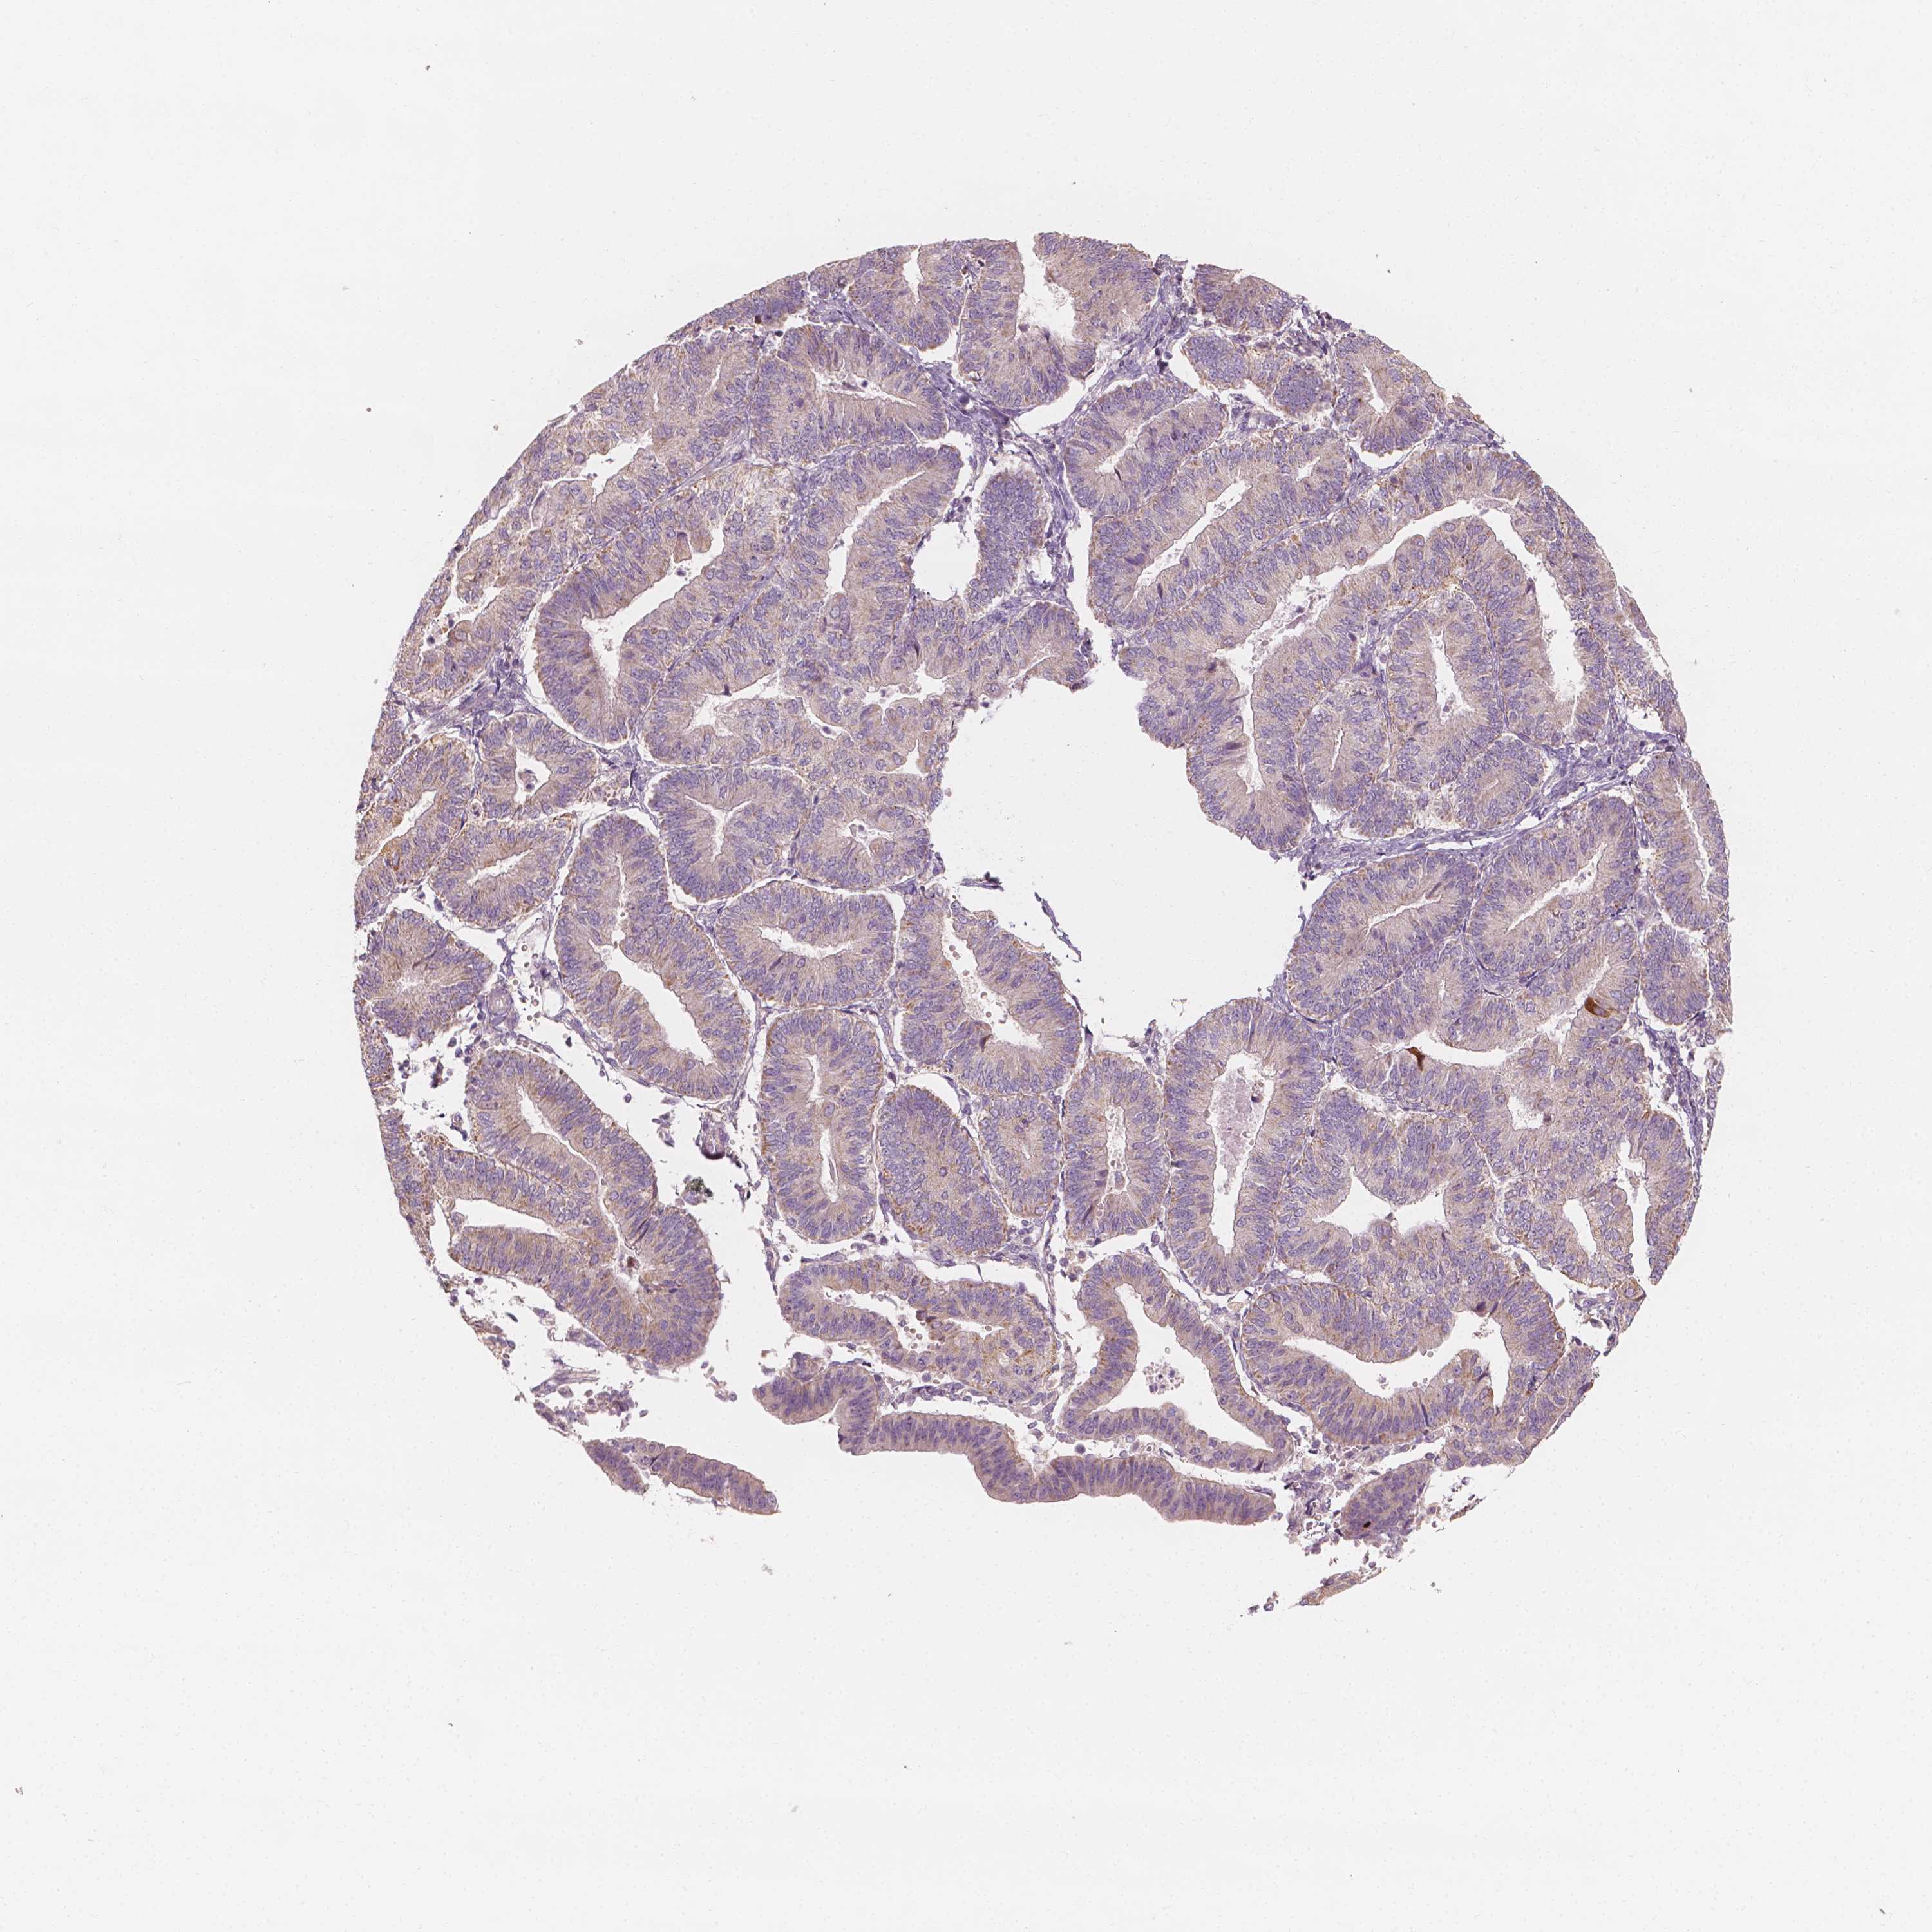

ENDOMETRIAL CANCER - Protein expressioni

A mouse-over function shows sample information and annotation data. Click on an image to view it in a full screen mode. Samples can be filtered based on level of antibody staining by selecting one or several of the following categories: high, medium, low and not detected. The assay and annotation is described here.

Note that samples used for immunohistochemistry by the Human Protein Atlas do not correspond to samples in the TCGA dataset.

Antibody stainingi

Antibody staining in the annotated cell types in the current human tissue is reported as not detected, low, medium, or high, based on conventional immunohistochemistry profiling in selected tissues. This score is based on the combination of the staining intensity and fraction of stained cells.

Each image is clickable and will lead to virtual microscopy that enables deeper exploration of all samples and also displays staining intensity scores, fraction scores and subcellular localization as well as patient and tissue information for each sample.

Antibody HPA024361

Antibody HPA064939

Staining

High

Medium

Low

Not detected

Intensity

Strong

Moderate

Weak

Negative

Quantity

>75%

75%-25%

<25%

None

Location

Nuclear

Cytoplasmic/membranous

Cytoplasmic/membranous,nuclear